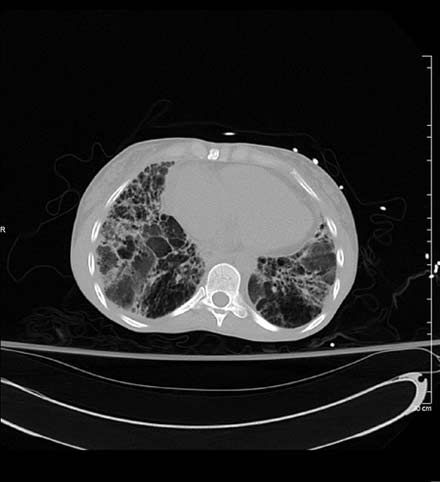

TC Torácica - Esclerodermia: Cambios confluentes fibróticos.

Nota: Las imágenes se muestra para fines ilustrativos. No trate de sacar conclusiones comparando esta imagen con otras en el sitio. Solamente los radiólogos calificados deben interpretar las imágenes.